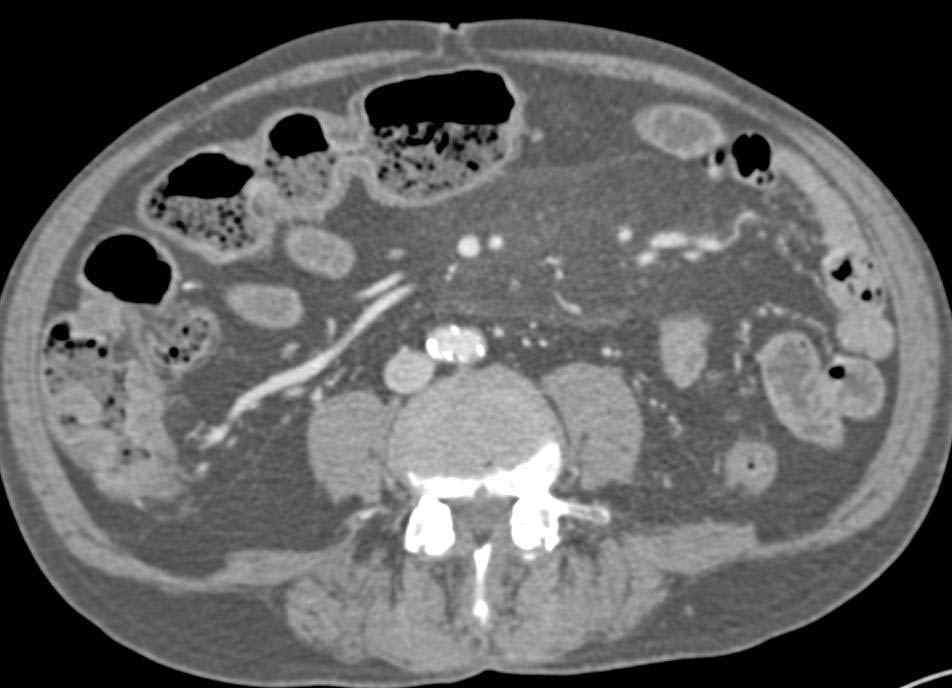

Панникулит брыжейки

Панникулит брыжейки 110 фото